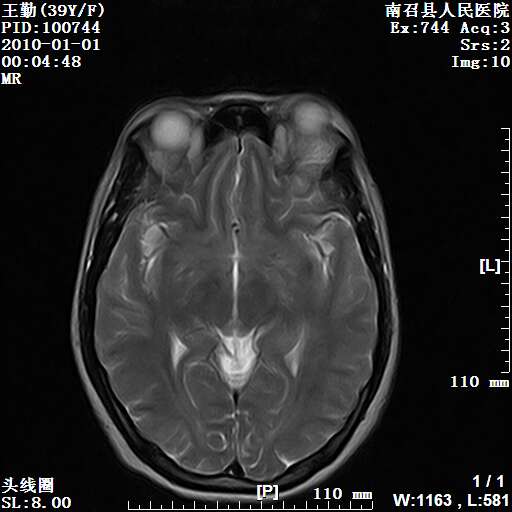

以下是引用随光逐影在2010-1-22 9:03:00的发言:[br]考虑左侧中颅窝(蝶骨翼区)脑膜瘤侵犯蝶骨翼并突入左侧眼眶。

以下是引用水过无痕在2010-1-22 14:55:00的发言:[br]一、定位:颅外占位;二、定性:恶性可能性大;三、组织来源:来源于左侧眼外直肌或其他部位;考虑为:横纹肌肉瘤>转移瘤>脑膜瘤.